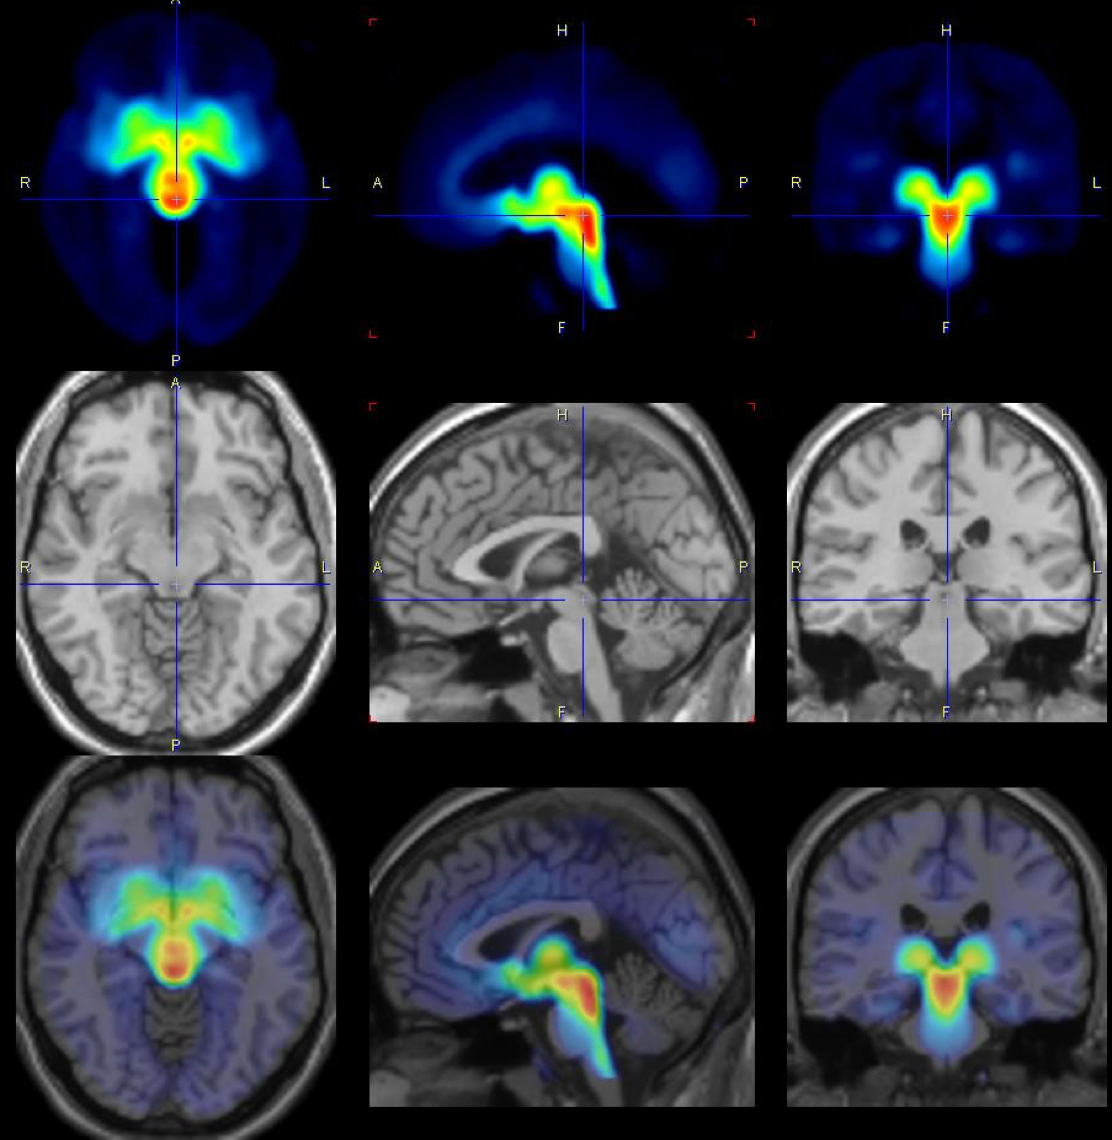

„Wir haben 30 Patientinnen und 29 gesunde Studienteilnehmerinnen über mehrere monatliche Zyklen hinweg untersucht und zu verschiedenen Zykluszeitpunkten Aufnahmen vom Gehirn mit Positronen-Emissions-Tomografie (PET) gemacht. Dabei haben wir herausgefunden, dass vor der Menstruationsblutung die Serotonin-Transporter-Dichte im Gehirn erhöht ist und damit einen Verlust von diesem Botenstoff im synaptischen Spalt begünstigt, der die affektiven Symptome bei den betroffenen Frauen auslösen kann. Dieser Befund ist überraschend, weil man bisher dachte, der Serotonin-Transporter sei ein individuelles Merkmal, das sich in einer derartig kurzen Zeitspanne von zwei Wochen nicht verändert - normalerweise geht man von nur geringfügigen Veränderungen alle 10 Jahre aus.“

Die WissenschaftlerInnen haben zu verschiedenen Zykluszeitpunkten Aufnahmen vom Gehirn der Frauen mit Positronen-Emissions-Tomografie (PET) gemacht.